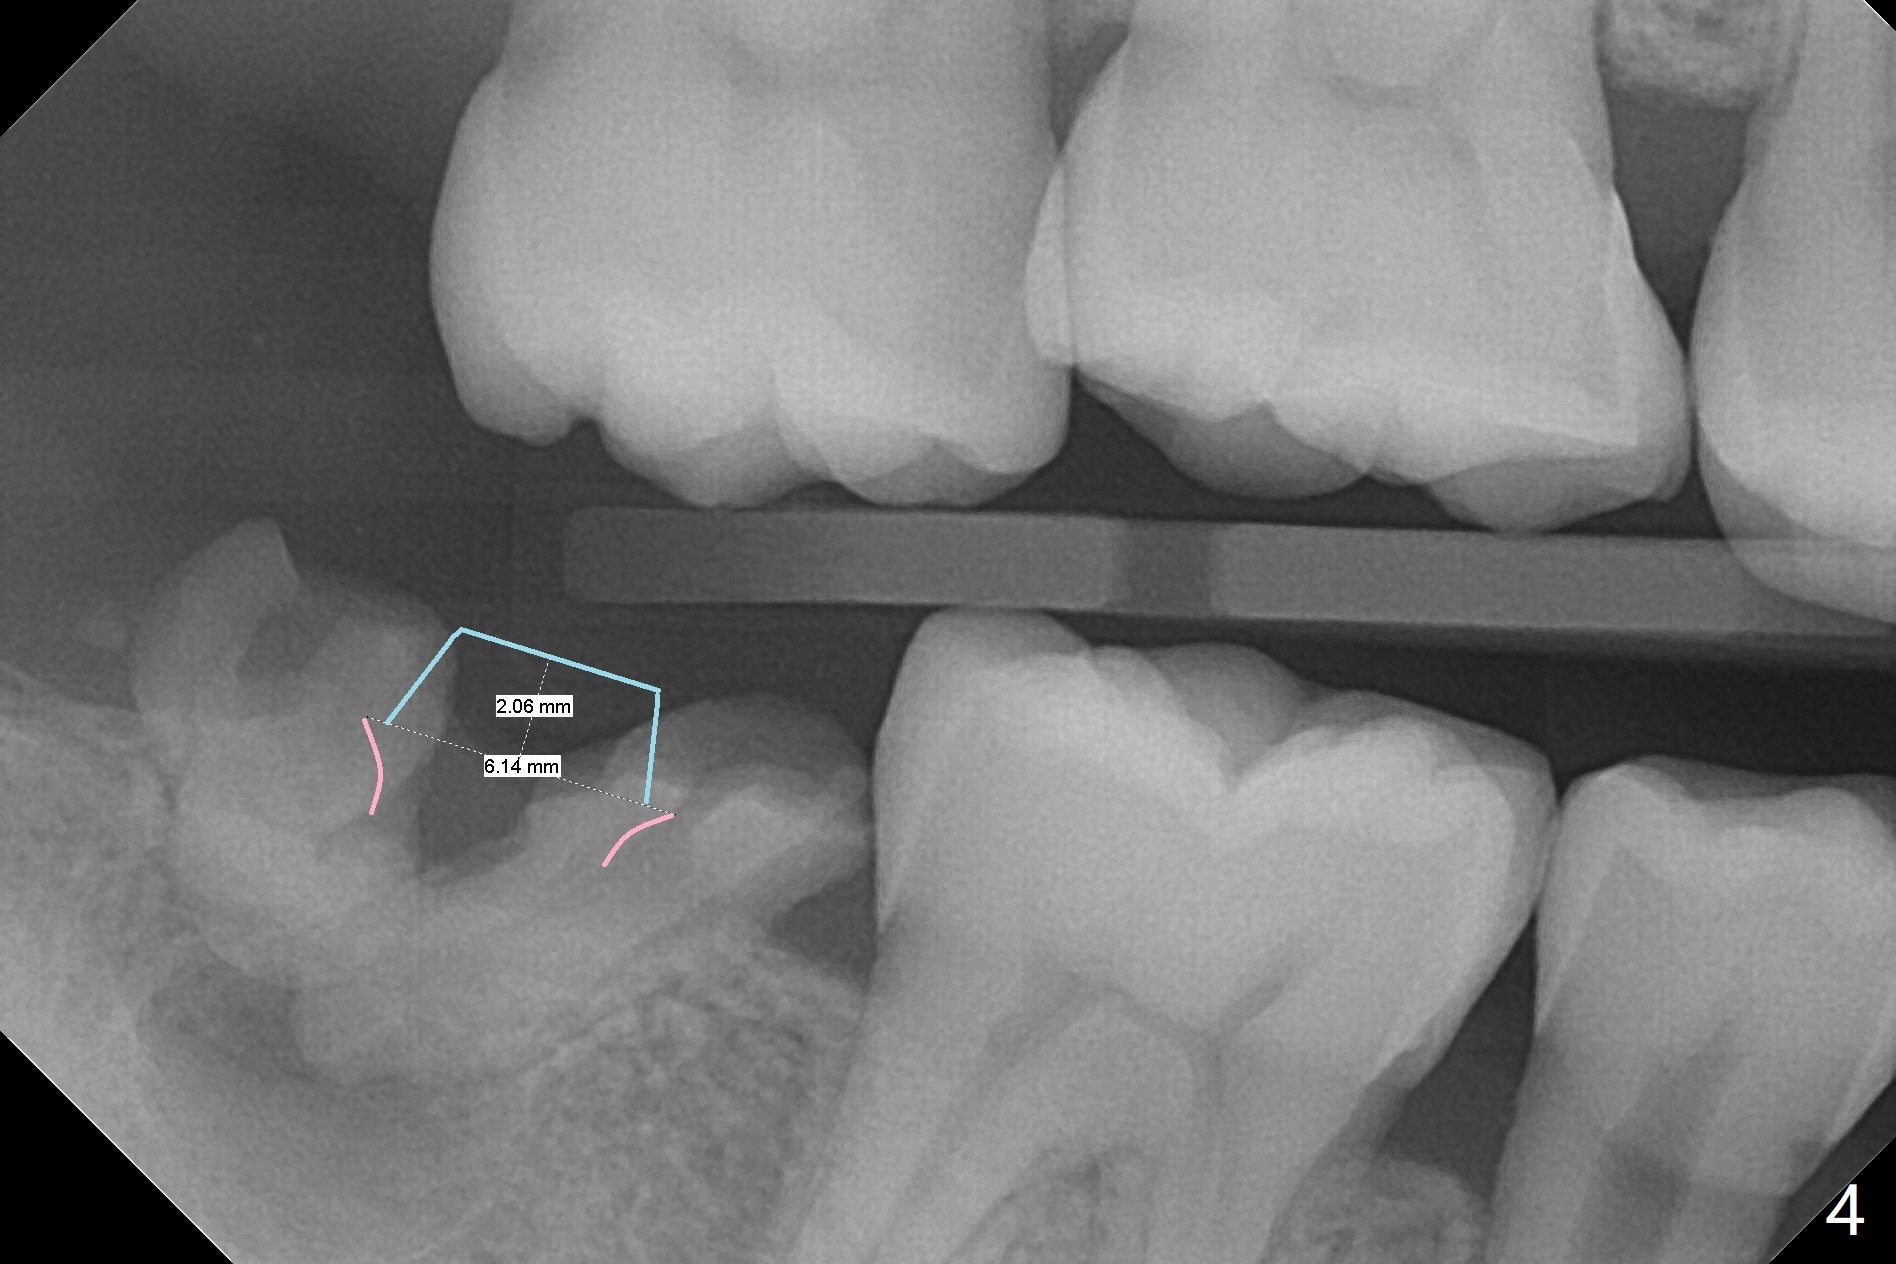

A 39-year-old man finishes orthodontic treatment without intrusion of the upper 2nd molar (Fig.1). He is reluctant for mini-implant placement for intrusion. After extraction of the tooth #31 with periapical radiolucency (Fig.2 *), a 5x11(4) mm Magicore will be placed with guide (Fig.3). Following osteointegration (Fig.4), a burn out core is going to be placed (Fig.5 brown, inside metal, outside plastic). With proper height adjustment, a provisional is fabricated around the core with acrylic (Fig.6 white). If the provisional keeps breaking down under occlusion, the case will be sent to lab for a screw retained crown with unfinished rough occlusal surface so that a thin layer restoration material able to be laid chair-side (acrylic or suction down material). Over time, the opposing tooth will be intruded (Fig.7 arrow).